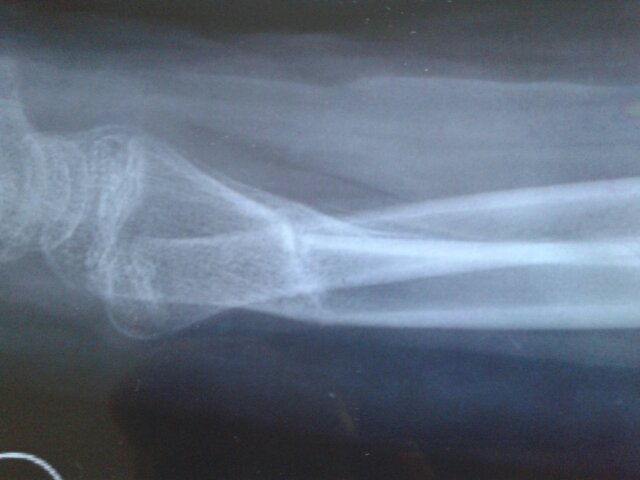

15岁男孩,左桡骨远端骨折,两月拍片有成角,现在胳膊向背拱,而且腕关节向上有卡住似的,怎么锻炼能使 15岁男孩,左桡骨远端骨折,两月拍片有成角,现在胳膊向背拱,而且腕关节向上有卡住似的,怎么锻炼能使胳膊改善,跪求。别说套话,我把照片发给大家看下,求指点 点击展开 匿名用户 2016-03-10 09:25 推荐回答 用筷子夹豆子花生练习…如果不行就用手捡小石头仍小石头缺乏功能锻炼…我的医命征亲戚比你大件泳孩子还惨…咬牙蒸常坚持锻炼过来了 匿名用户 2016-03-10 09:32 宝宝知道提示您:回答为网友贡献,仅供参考。 相关问题 左桡骨远端骨折2月的片子,现15岁男孩左胳膊向背拱,而且关节向上时有东西卡住似的,该如何? 肩部胳膊酸痛,受凉引起锻炼身体还是痛请问? 宝宝还不到俩月,宝儿躺着时婆婆经常双手提拉宝宝胳膊,目的是锻炼宝儿起身抬头,这麽大幅度锻炼对吗?难道不容易造成肩关节脱臼吗?